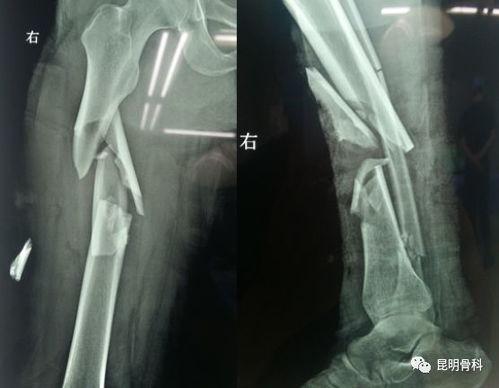

1. 外观畸形

看看这张照片,是不是觉得小腿的形状有点奇怪?这就是骨折后的外观。由于骨头断裂,小腿可能会出现弯曲、扭曲,甚至出现畸形。这种外观畸形,不仅影响美观,还会给患者带来极大的痛苦。

2. 手术治疗

对于一些严重的小腿骨折,可能需要手术治疗。手术方法包括切开复位、钢板固定等。